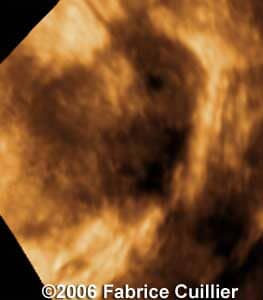

These are some cases of ectopic pregnancy (GEU) using the 2D and 3D scans.

Case 1